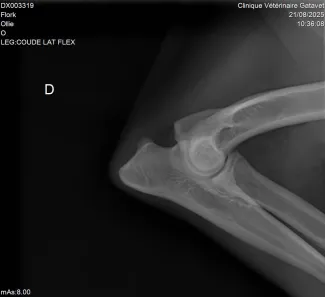

Un examen vétérinaire avec radiographie permettra de confirmer ou non le diagnostic.